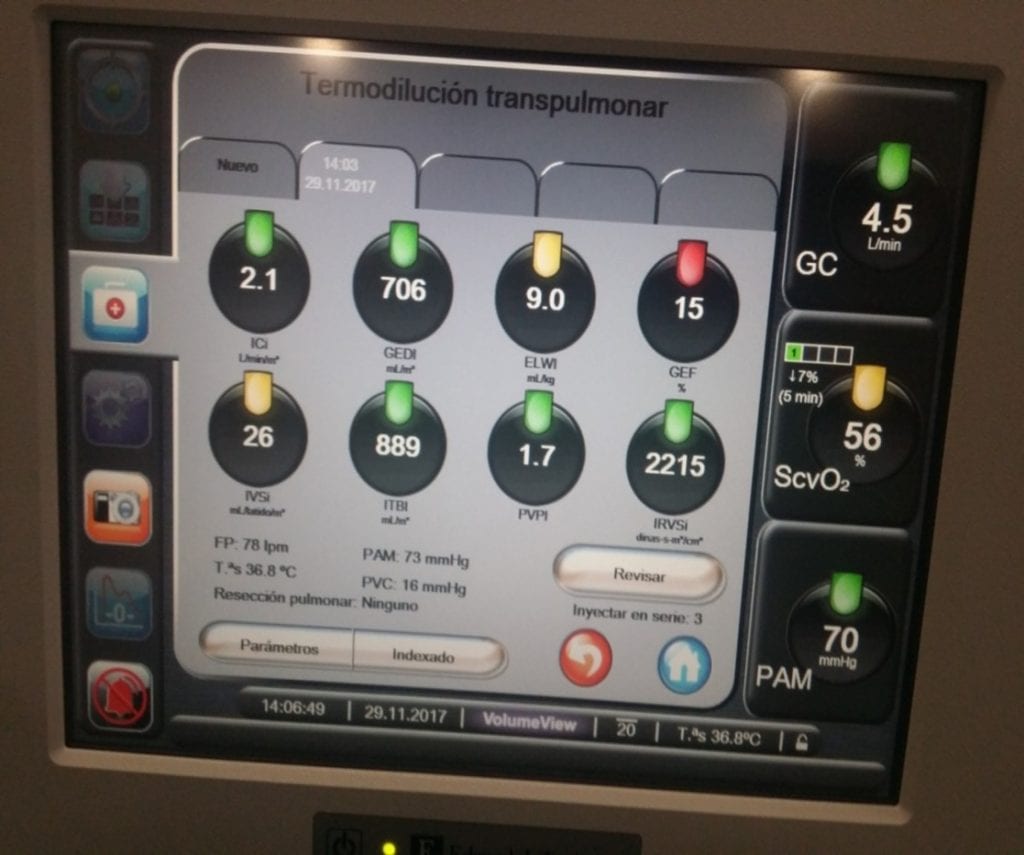

El protocolo o diagnóstico para seguir en casos de sobrecarga de volumen (volume overload) y SDRA (Síndrome de Distrés Respiratorio Agudo) se basa en ELVW y VS.

A la hora de detectar el trigger de la hipoperfusión, debemos fijarnos en los siguientes parámetros: CO, ELVW, VS, RCT y VPP.

- TDI: guía la terapia con diuréticos y fluidos. EVLW validado al contrastarlo con gravimetría. Asumimos que el volumen de sangre pulmonar es el 20-25% del GEDV (Sakka, 57 PAC críticos). Estimamos, no es una medida precisa.

– Determinar por Volume View o sistema Picco

– Índice de permeabilidad vascular y Agua Extrapulmonar